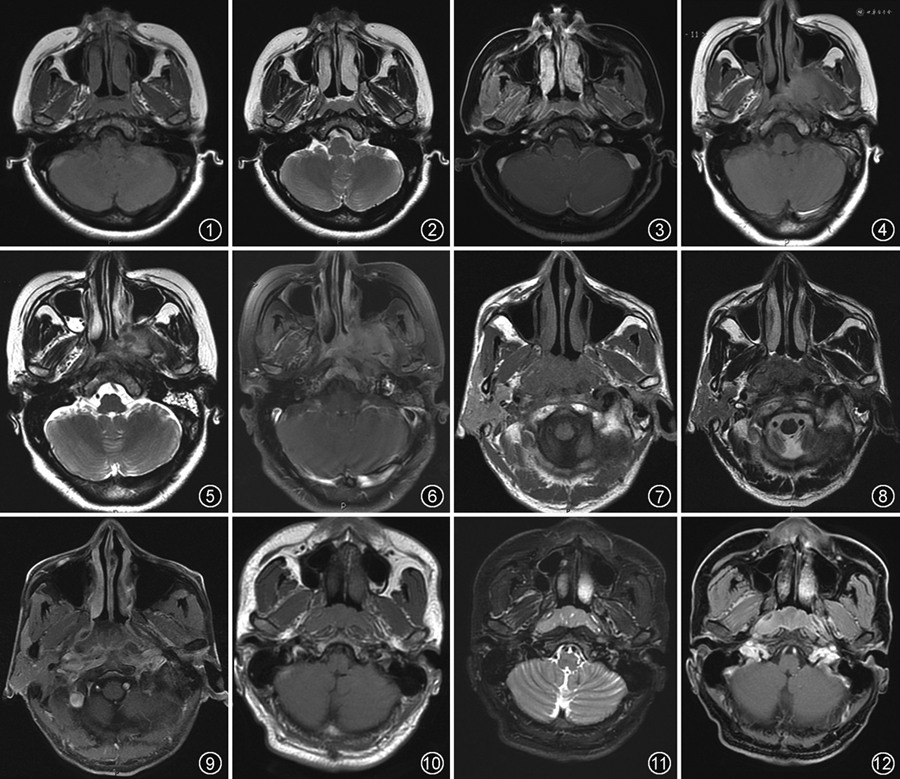

影像诊断要点:CT上鼻咽肿块多呈等密度,与周围肌肉密度相仿,较少有囊变、钙化;肿块与周围组织分界不清,增强扫描呈中度强化。早期鼻咽黏膜增厚,中晚期可形成软组织肿块,T1WI呈等或低信号,T2WI呈高信号但低于黏膜信号,DWI有明显扩散受限,增强扫描呈中度强化。鼻咽形态不对称,表面粗糙不平,咽隐窝变浅、消失;咽旁间隙受累表现为周围脂肪界面消失、肌肉受侵;向上破坏颅底骨质并侵入颅内,颅底骨质破坏表现为高信号黄骨髓被低信号肿瘤组织取代,颅内侵犯常累及海绵窦、颞叶及桥小脑角区。颈部淋巴结转移多表现为由上而下循序性,咽后淋巴结为首站转移淋巴结,远处转移可转移至骨、肺、肝等[6](图7~9)。

影像诊断要点:鼻咽双侧性受累,受累广泛但较为表浅,可表现为咽淋巴环广泛增厚,鼻咽腔狭窄。CT呈均匀等密度,无钙化、囊变、坏死。MRI T1WI呈等低信号,T2WI呈等高信号,DWI有明显扩散受限,信号均匀,增强呈轻-中度强化。肿块与周围组织结构分界清楚,咽旁间隙清晰,多无颅底骨质破坏[8, 9]。淋巴结多广泛肿大,淋巴结密度、信号与肿块一致,且较少发生坏死(图10~12)。